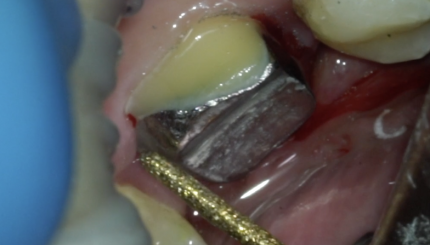

12,11,21,22 Замена билдапа,финишное препарирование+оттиск